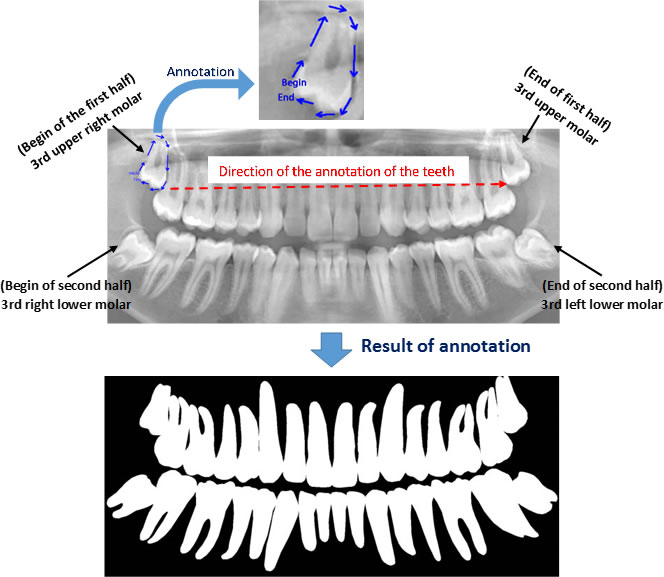

Image annotation

The process of annotating the images of our proposed data set occurred in two parts. First, it was initiated by the upper jaw through the annotation of the third right upper molar and making the annotation of all the teeth of the upper arch to the third left upper molar. Then, the same process was performed on the lower jaw with all the teeth, and in the same direction as the upper jaw, from left to right, starting with the annotation of the third right lower molar, and annotating all teeth from the lower arch to the lower third molar. Figure 4 illustrates the tooth annotation process through a panoramic X-ray image of the data set.